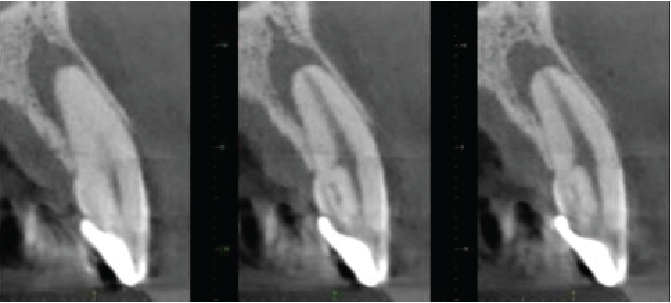

Cross sectional images of UR2

Mesio-distal

Labio-palatal

Axial

The UR2 is incompletely erupted, with its cervical margin more superiorly placed than on adjacent teeth, with the periodontal bone level correspondingly placed. The tooth is crowned. Dens invaginatus anomaly also seen (Oehler type I), matching that on the contralateral tooth. There is extensive external cervical root resorption arising distally, with a large surface defect and with root canal involvement. The difficulty in seeing the periodontal ligament around the apical half of the root probably indicates some areas of ankylosis. No periapical inflammatory pathosis.